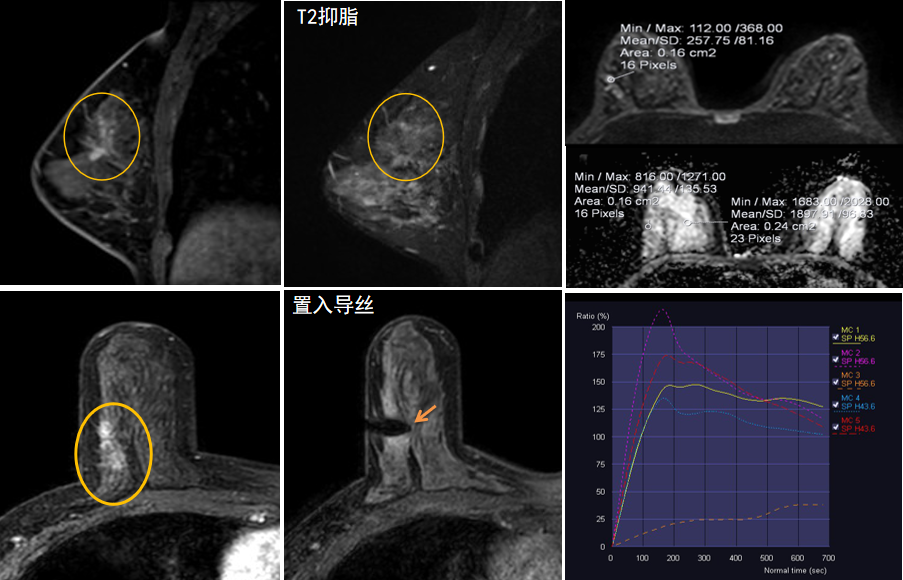

今年45歲的某女士,兩個月前行超聲檢查發(fā)現(xiàn)右乳結(jié)節(jié),乳腺X線攝影檢查提示右乳外上象限局部腺體結(jié)構(gòu)扭曲并簇狀無定形鈣化,為了進(jìn)一步評估病變性質(zhì)并確定范圍進(jìn)行了乳腺MR平掃 DWI 增強的檢查,經(jīng)MR評估發(fā)現(xiàn)右乳病變范圍較廣,評估為BI-RADS 4類可疑病變,需要取得病理學(xué)結(jié)果。

只能借助影像學(xué)引導(dǎo),但超聲僅顯示了病變中的小結(jié)節(jié),X線攝影(鉬靶)顯示的病變邊界比較模糊,要想做到精準(zhǔn)完整切除必須借助MR的引導(dǎo),而這一技術(shù)對軟硬件平臺及人員技術(shù)都有很高的要求,因此,多年來一直是我國乳腺病變診療的盲區(qū),經(jīng)常是MR發(fā)現(xiàn)可疑病變但卻無法處理。目前全國僅有少數(shù)幾家醫(yī)院開展了這方面的部分工作。

西安國際醫(yī)學(xué)中心醫(yī)院影像診療中心陳寶瑩主任團(tuán)隊有著十余年影像引導(dǎo)下乳腺介入診療的經(jīng)驗,借助醫(yī)院高精尖的MR平臺,成為西北首個全面展開MR引導(dǎo)下各項乳腺介入診療技術(shù)的團(tuán)隊,能夠?qū)Τ暭叭橄賆線無法顯示或顯示不清的病變進(jìn)行MR引導(dǎo)下的導(dǎo)絲定位、穿刺活檢及真空輔助旋切。

陳寶瑩主任及其帶領(lǐng)的MR介入診療小組詳細(xì)詢問了病情,分析了患者資料,并與患者和臨床醫(yī)生進(jìn)行了充分溝通,確定于手術(shù)前為患者實施MR引導(dǎo)下的病變穿刺導(dǎo)絲定位和體表范圍確定。手術(shù)前陳寶瑩主任帶領(lǐng)聶品醫(yī)師、馬小偉技師、韓愛萍護(hù)士長等MR介入診療小組成員,借助MR高清的圖像顯示和定位系統(tǒng),確定病變范圍,精準(zhǔn)穿刺置入定位導(dǎo)絲,并準(zhǔn)確標(biāo)記出病變體表范圍,整個過程患者無任何不適。在定位導(dǎo)絲和體表范圍標(biāo)記的輔助下,甲乳外科劉曉敏主任精準(zhǔn)切除了病變,解除了患者的后顧之憂。

國內(nèi)外指南均建議40歲以上的女性每年行一次雙乳X線攝影(鉬靶)檢查,以篩查乳腺癌。對于乳腺癌高危人群40歲以前即建議開始乳腺癌篩查,除了進(jìn)行乳腺X線攝影(鉬靶)篩查外需要補充MR檢查,MR檢查敏感性最高,能夠發(fā)現(xiàn)大量X線攝影和超聲檢查陰性的可疑病變,基于多模態(tài)、多參數(shù)的結(jié)構(gòu)和功能成像的基礎(chǔ)上,MR能夠精準(zhǔn)顯示病變位置、范圍以及病變內(nèi)的活性區(qū)域,MR引導(dǎo)下的介入診療不但解決了僅在MR顯示的病變的處置難題,而且能夠精準(zhǔn)定位活性區(qū)域,保證了定位、活檢及旋切的準(zhǔn)確性。